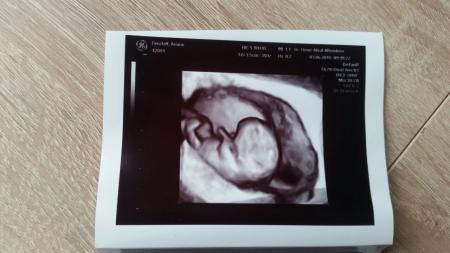

Heute war ich beim Frauenarzt.. ja ich weiß ist doch recht ungewöhnlich aufn Sonntag... war auch eher Ausnahme... mir wars recht so konnt i mein krümel wiedersehen... dieses mal hat der arzt aber leider bauchultraschall gemacht... leider sind die bilder nicht soooo schön geworden.... Was aber toll ist war das das mein krümel von rücken- liege-position auf bauchschwimmen dann auf sitz-position immer hin und her ist... war schön anzusehen... Herz ist top... schlägt kräftig Ich werd mal n bild mit ranhängen..aber wie gesagt sind leider nicht so schön dies ma...

Ja er hat mir die besten Bilder mitgegeben... ich freue mich eig immer über jedes Bild... zu sehen was sich verändert hat...einfach zum dahin schmelzen

Wow, die Bilder sind ja schön. Meine Ärztin hat kein so tolles Gerät. Also seid froh darüber. Schön, dass es deinem kleinen Schatz gut geht.

Wow! So tolle Bilder hab ich noch nicht von unserem Krümelchen. Das erste 3D Bild wird wohl erst nächstes mal gemacht. (3.7.)